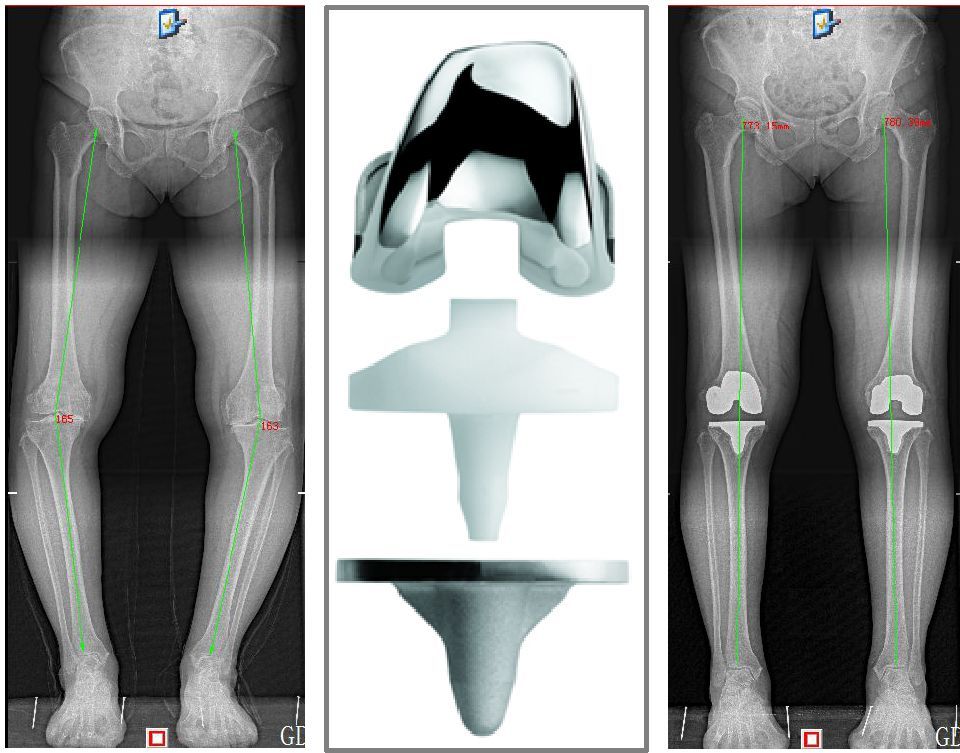

单髁置换术

对于年龄大于55岁、内侧间室关节炎、关节活动度尚可、关节内畸形的患者,可以进行单髁置换术,能解决关节内磨损,去除病损部位,矫正畸形,缓解疼痛,进而改善关节功能,避免膝关节骨关节炎进一步进展。

全膝关节置换术

对于一些膝关节疼痛明显、畸形严重、磨损超过两个关节间隙的患者,以及一些少见的关节炎如类风湿性关节炎、风湿性关节炎等,可以进行全膝关节置换术,去除膝关节表面磨损硬化软骨及增生骨质,能有效减轻疼痛,恢复关节功能。